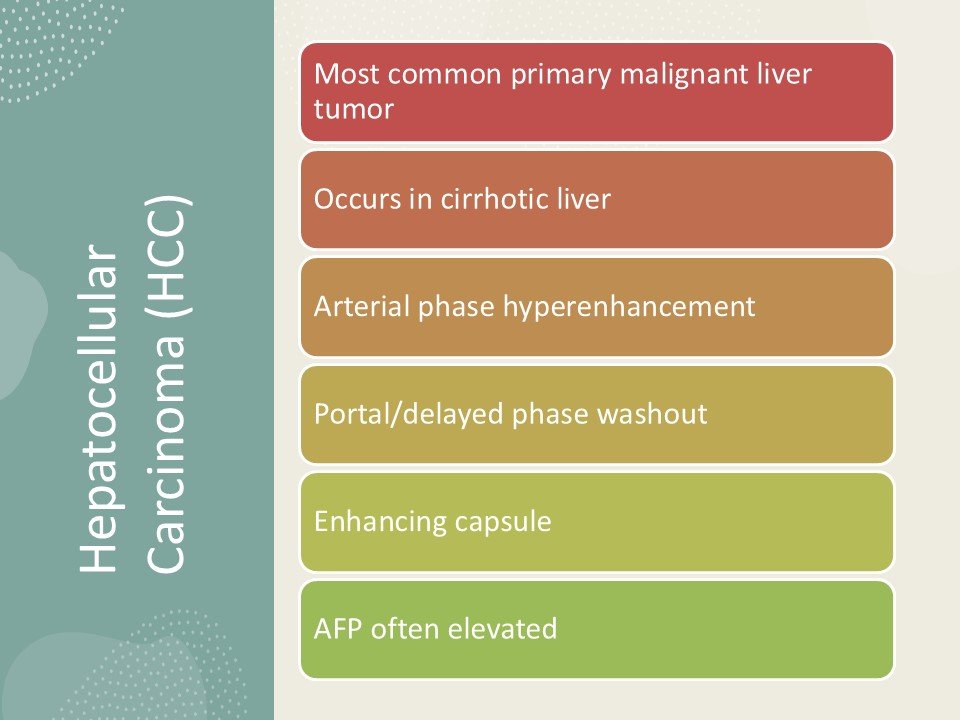

CT and MR images in a 37-year-old male with poorly-differentiated HCC with histological capsule. METAVIR score of the background liver was F3. In contrast-enhanced CT, a 49-mm observation shows (a) nonrim APHE on arterial phase and (b) nonperipheral washout with an enhancing capsule on equilibrium phase. In gadoxetic acid-enhanced MRI, a 48-mm observation shows (c) nonrim APHE on arterial phase, (d) nonperipheral washout on portal venous phase, and (e) TP hypointensity with suspicion of an enhancing capsule on transitional phase. Hepatobiliary phase image clearly shows (f) a nonenhancing capsule surrounding the observation.

(a) unenhanced, (b) Arterial, (c) portal, and (d) delayed phases. After intravenous contrast administration, the nodule shows stable peripheral rim-like enhancement (arrow).

T2 :Hypo to slightly hyperintense

Central scar

A 33-year-old male patient with right hepatic haemangiosarcoma. (a) Unenhanced CT image shows a lobulate mass with an indistinct boundary in the right lobe. (b–d) Enhanced CT images of the arterial, venous, and delay phases showed a heterogeneous centripetal enhancement of the mass, and the contrast agent did not completely fill in the lesion at the end.

T1 C+ (Gd)

heterogeneous enhancement with progressive filling

irregular flame-shaped pattern

Target appearance